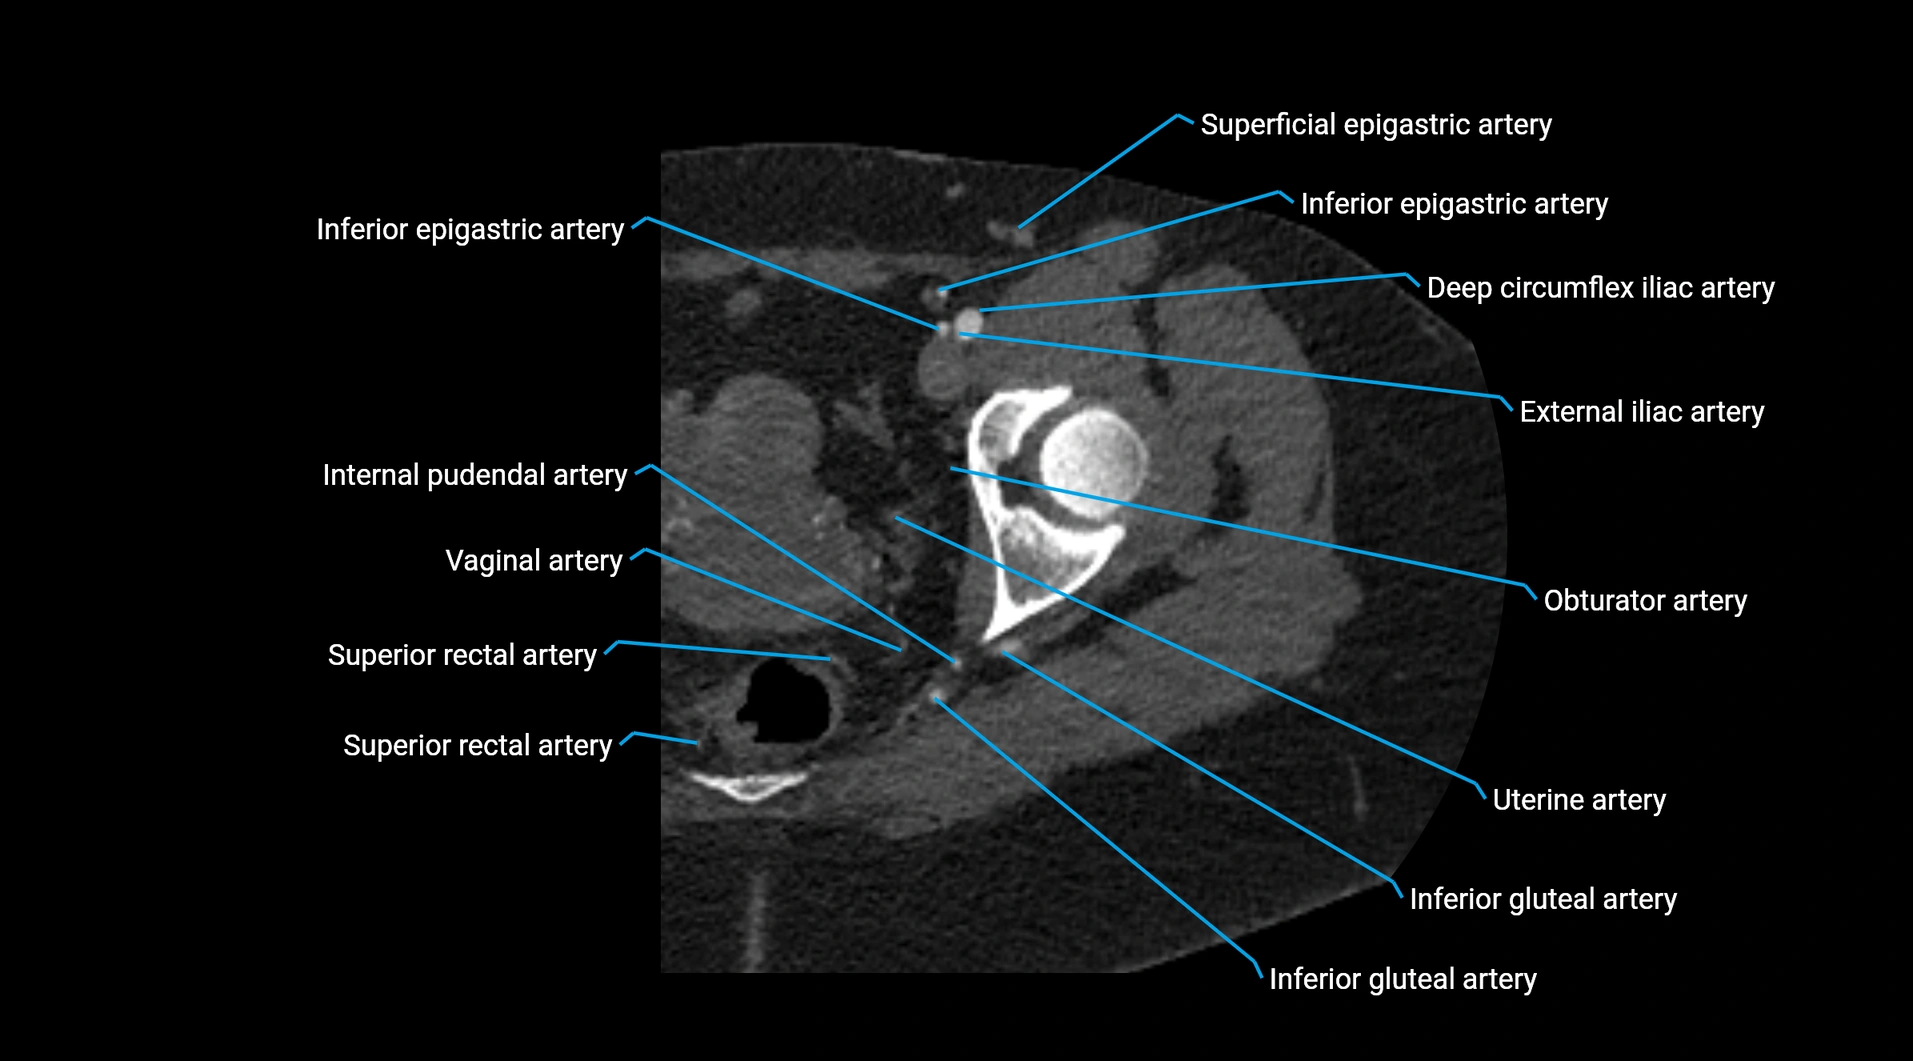

CT images

image

Contrast-enhanced CT (CTA):

• Gold standard for abdominal aortic imaging

• Provides excellent detail of lumen, wall, aneurysm, thrombus, and branch vessels

• Multiplanar and 3D reconstructions help in aneurysm measurement, stent graft planning, and dissection evaluation